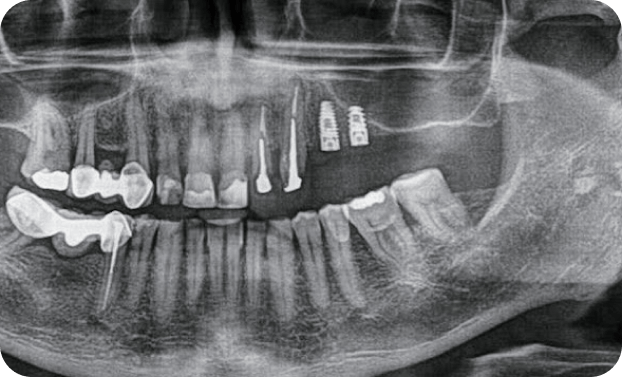

Casos